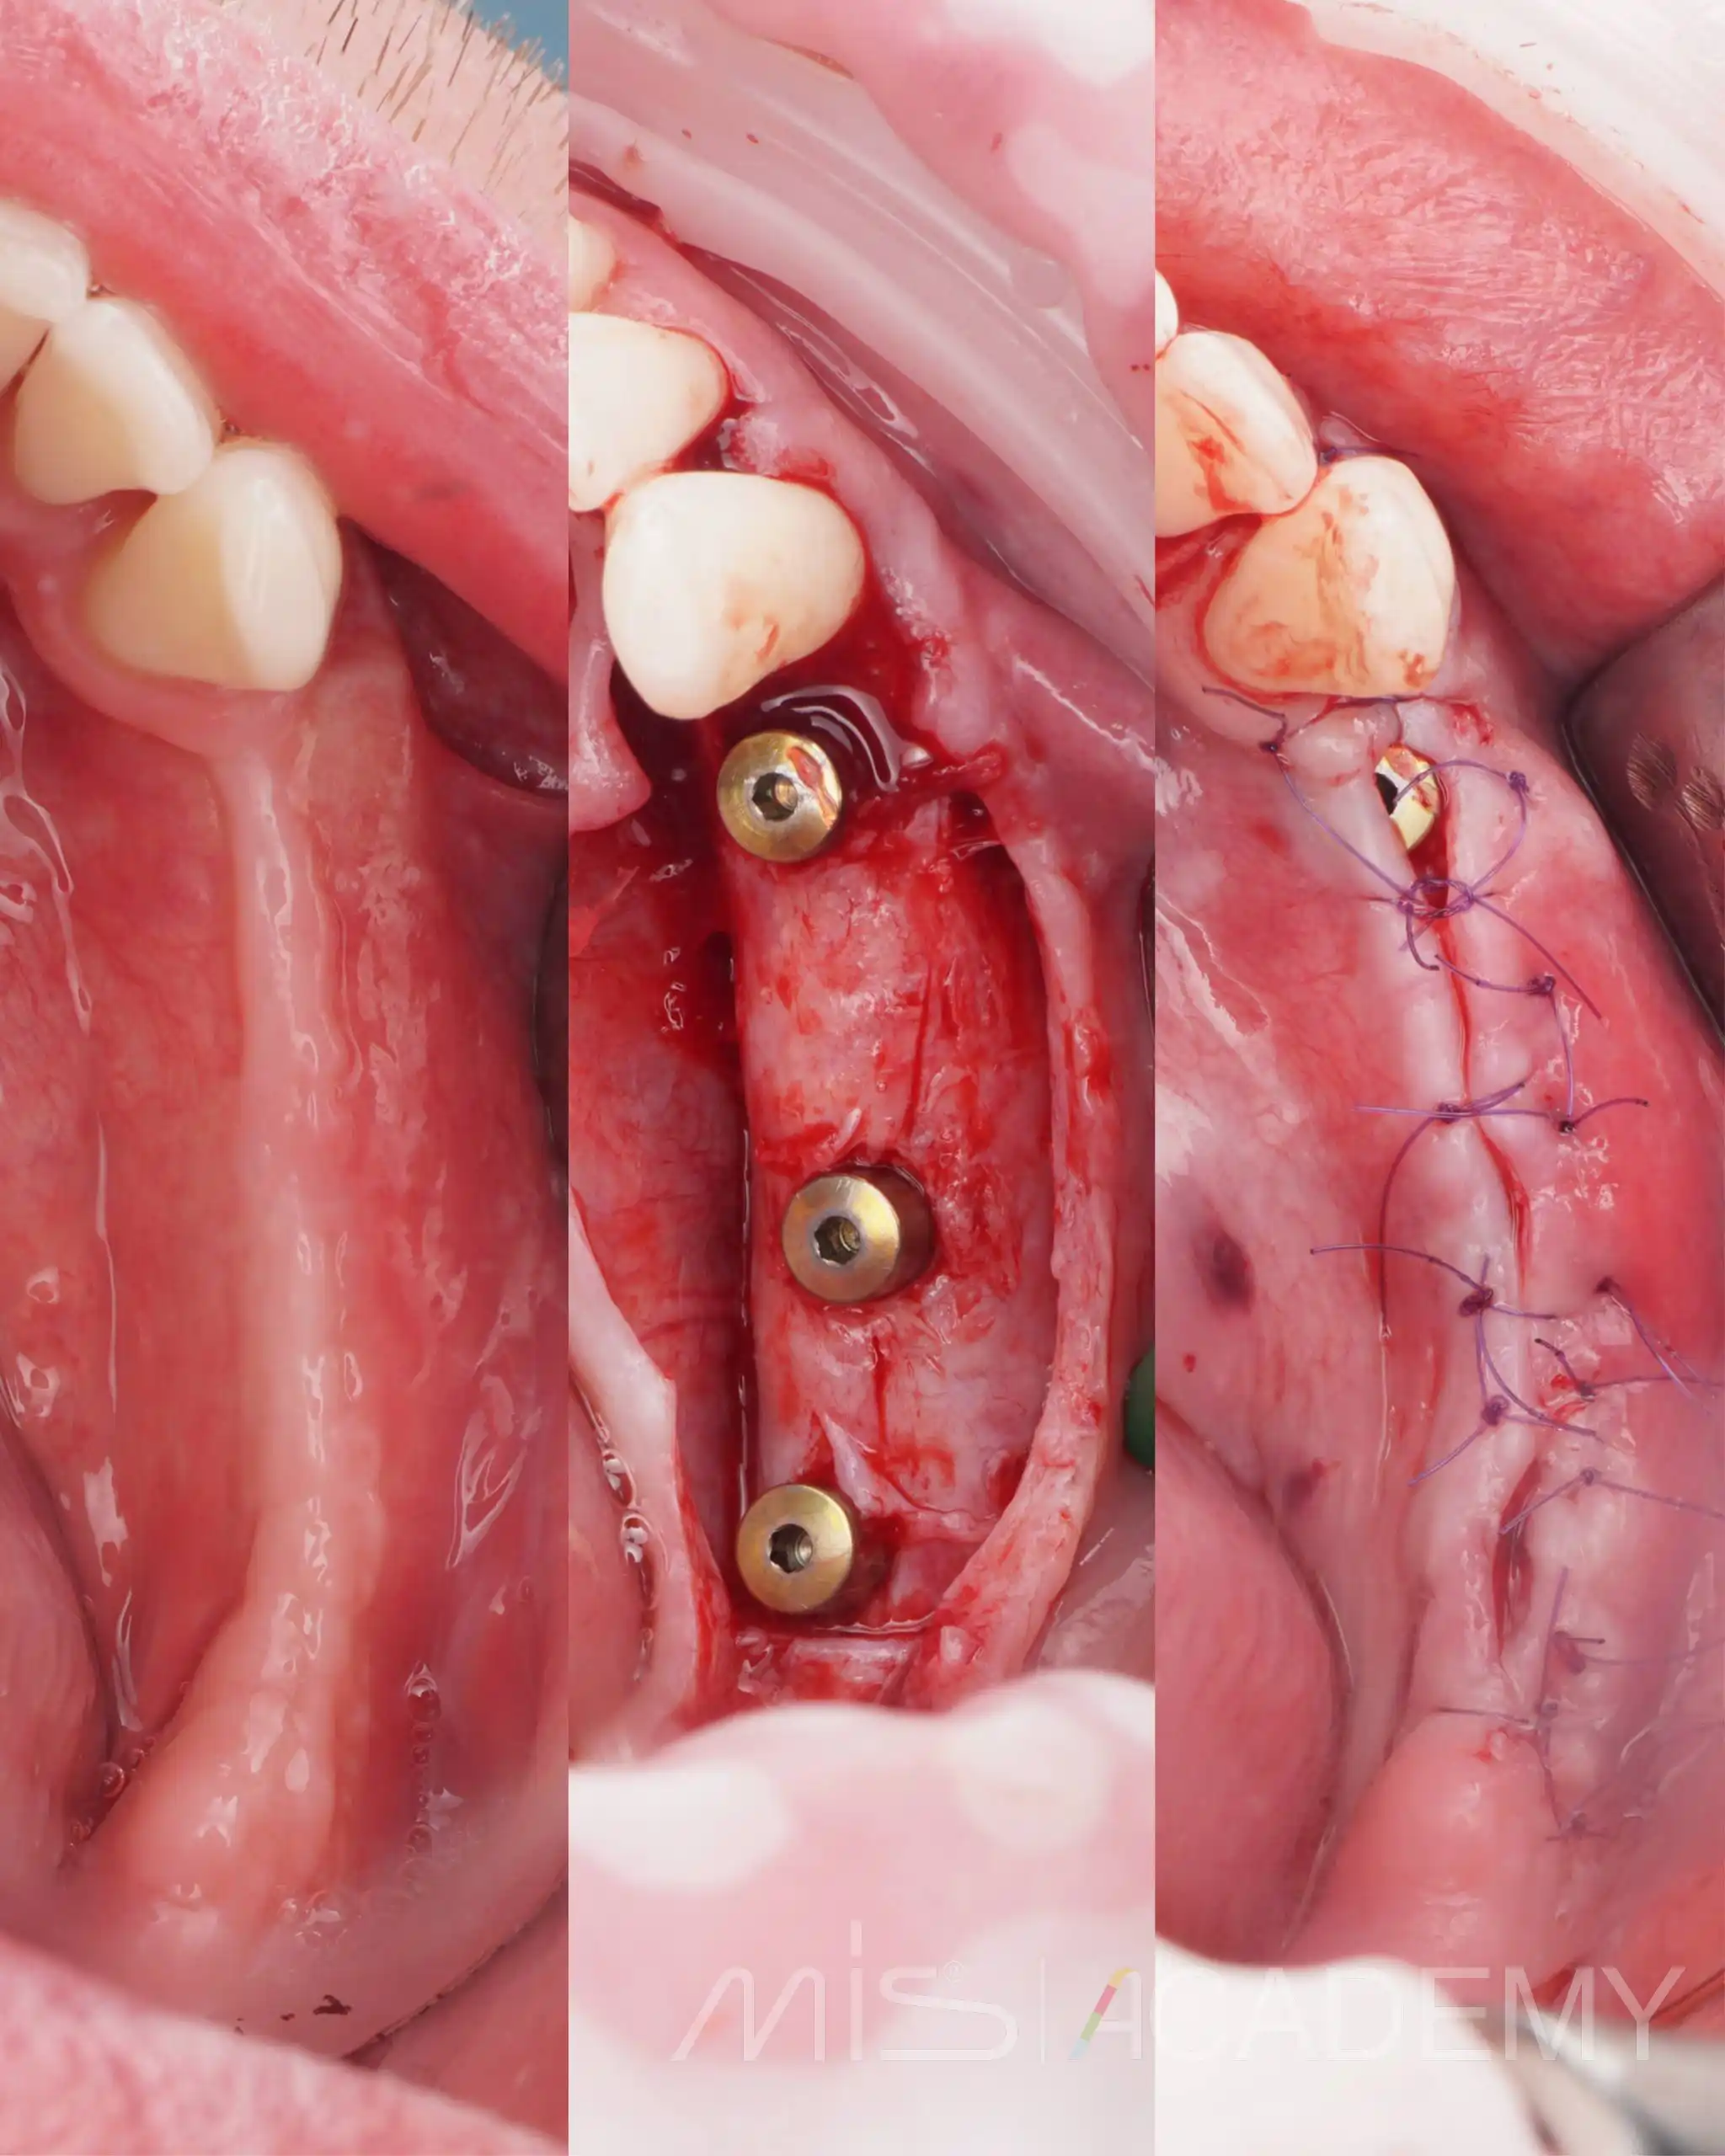

Второй этап нижняя челюсть:

В боковых отделах выраженная атрофия по ширине и высоте. При планировании приняли решение об имплантации с одновременной костной аугментацией по ширине.

— Установлены имплантаты MIS C1.

— Connect абатменты с заглушками, которые дополнительно сработали как тенты.

— Костная пластика материалами Osteobiol: справа ксено MP3 с Derma, слева Gen-Os с нативным коллагеном и Lamina Curved, ушивание.

Через 6 месяцев выполнено раскрытие, замена заглушек на формирователи десны на коннектах и пластика мягких тканей.